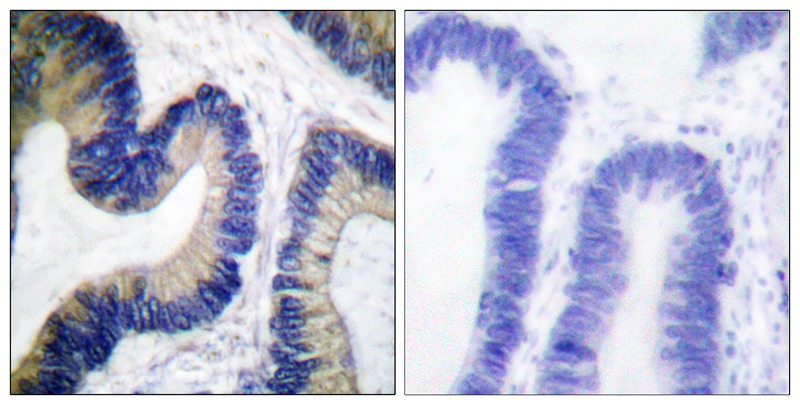

Immunohistochemical analysis of paraffin-embedded human colon carcinoma tissue using 4E-BP1 (Phospho-Ser64) antibody #12124. The picture on the right is treated with the synthesized peptide.